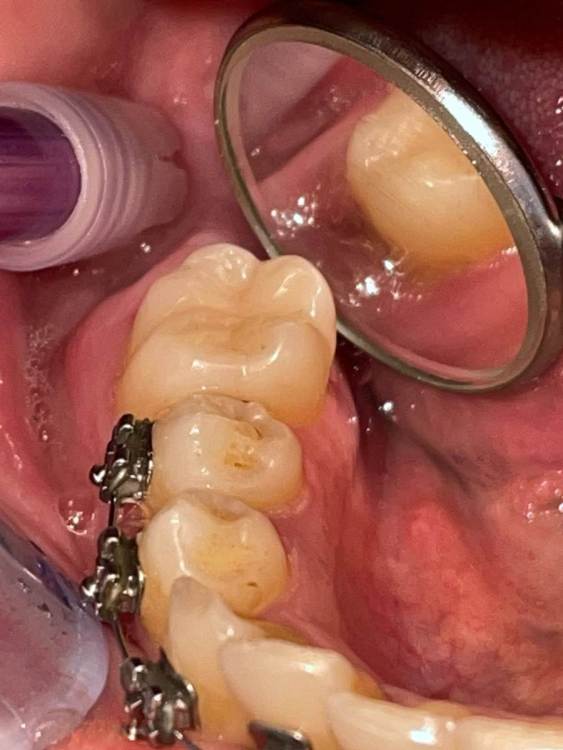

Graf Опубликовано 26 августа, 2023 Поделиться Опубликовано 26 августа, 2023 Пациентка пришла с жалобами на пульсирующие боли и небольшую опухлость в области 46 зуба. Что можете сказать по данному случаю и есть ли возможность сохранить этот зуб? Ссылка на комментарий